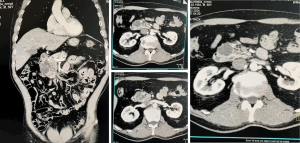

Patient 3, a 60-year-old female, presented with recurrent epigastric pain and was diagnosed with pancreatitis. Imaging with CT and positron emission tomography (PET)-CT suggested an IPMN in the pancreatic head, leading to consideration for pancreaticoduodenal resection. To refine the diagnosis, EUS revealed a 30 mm × 40 mm lesion with increased blood flow, thickened walls, and heterogeneous contents, resembling a post-necrotic pseudocyst (Figure 4).

Due to the patient’s coagulopathy (international normalized ratio 3.4), FNB and percutaneous biopsy was deemed unsafe. Instead, DAB indicated a CEA level of 52.73 ng/mL, suggesting a low likelihood of malignancy. Subsequently, transgastric stenting of the cyst was performed, allowing extraction of debris and purulent material, which confirmed its post-necrotic origin following acute pancreatitis. After 8 months, a repeat CT scan showed no residual cystic cavity, and the stent was therefore removed.